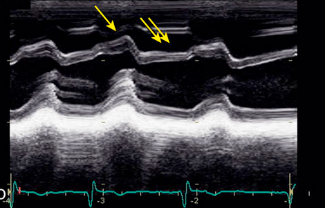

Oscillatory changes of the IVS

Constrictive pericarditis

What is the arrow pointing to?

What condition is this finding demonstrated in?